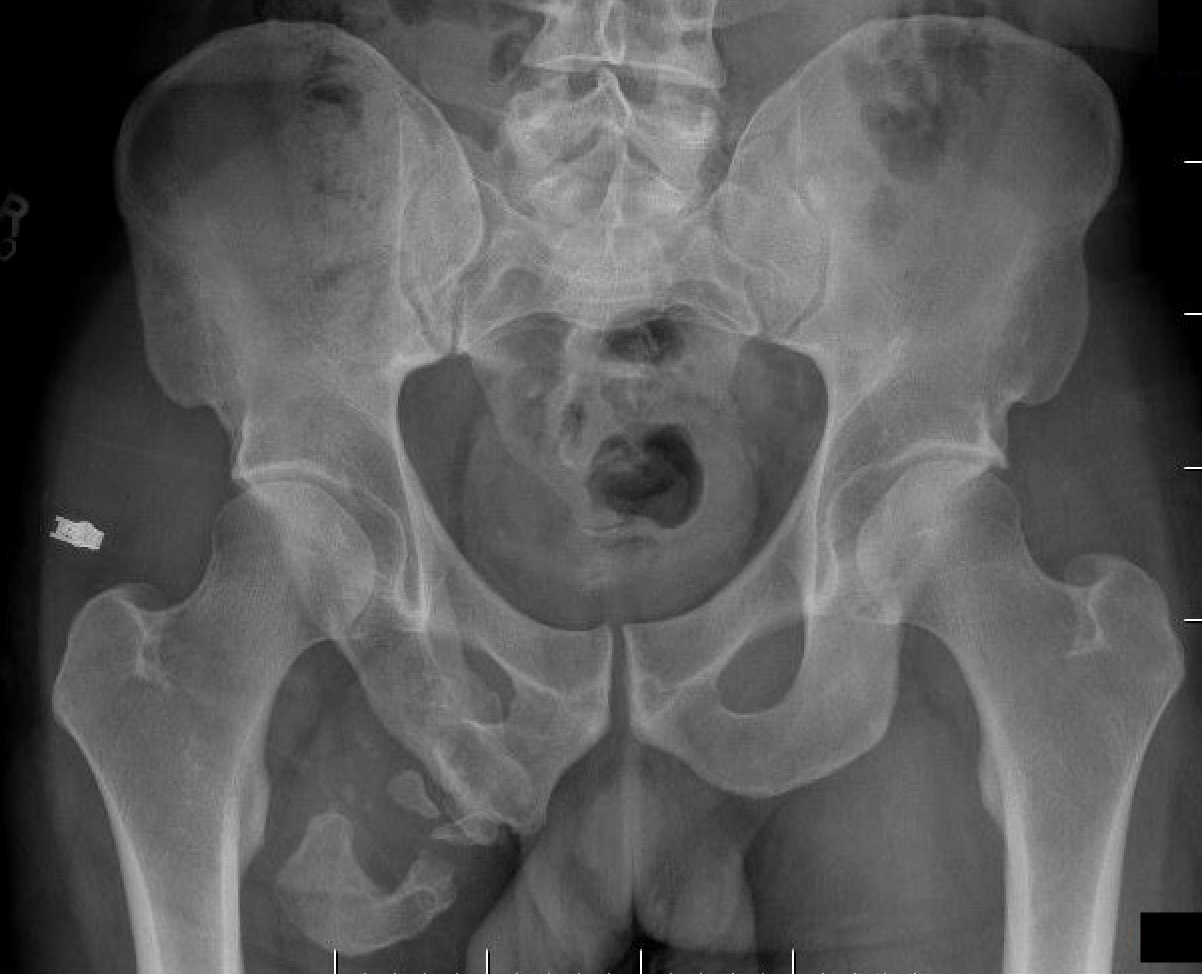

AIIS Avulsion

AIIS avulsion 1AIIS avulsion 2AIIS avulsion 3

Attachment

Rectus femoris